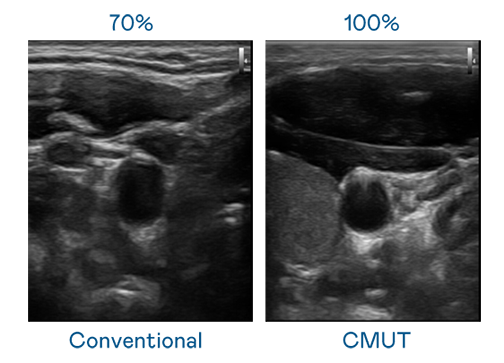

CMUT 技術是一種用電容式微機電元件來產生超音波訊號的技術。與傳統 PZT 壓電式技術相比,CMUT 頻寬增加 30%,更寬頻的超音波訊號讓影像解析度大幅提升,是實現高影像品質醫療超音波掃描、促進精準醫療發展的關鍵技術。

大頻寬帶來超清晰影像

超音波影像的解析度高低,首先取決於探頭能發出的訊號頻寬。ks凯时 CMUT 可提供高清晰的超音波訊號,提供高頻寬、高靈敏度、影像紋理細節更高的超音波影像,協助醫護人員縮短影像判讀時間及利用精準的醫療影像進行診斷。